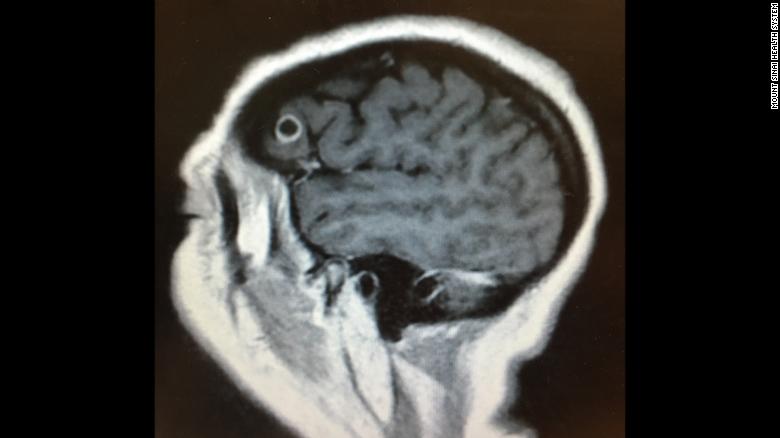

“They said, ‘If you’re not actually having a brain bleed, then it’s not actually an emergency,’ ” she said. A seizure disorder was also investigated and quickly dismissed. On a brain scan, Palma’s primary care physician detected a small lesion in the left frontal lobe of her brain and immediately sent her to Dr. Jonathan Rasouli, chief resident of neurosurgery at Mount Sinai Hospital in New York City, and his colleagues.

“We decided it would probably be in her best interest to do a biopsy of this lesion,” said Rasouli based on the fact that she was healthy and young and was having symptoms that he could directly correlate to the location of the lesion.

Besides, she had no risk factors for anything else that might explain the presence of a brain lesion. Rasouli carefully explained the possibilities to his patient. “I was told that it was most likely a malignant tumor which would require radiation and chemo even after the surgery,” said Palma. The surgery would be risky because the location of her “tumor” was very close to the brain region that controls speech.